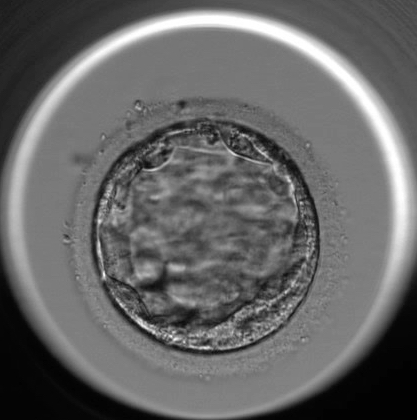

die BC hat den Expandierungsgrad 2 bis 3

die äußere Zellmasse hat etwas ungleichmäßige Strukturen , daher B/C

die innere Struktur kann ich auf dem Bild nicht gut genug erkennen, um sie einzustufen

insgesamt kann man sagen: ein guter Embryo, der sich zeitgerecht bis zum BC-Stadium

entwickelt hat, dessen Qualität mit B beschrieben werden kann.